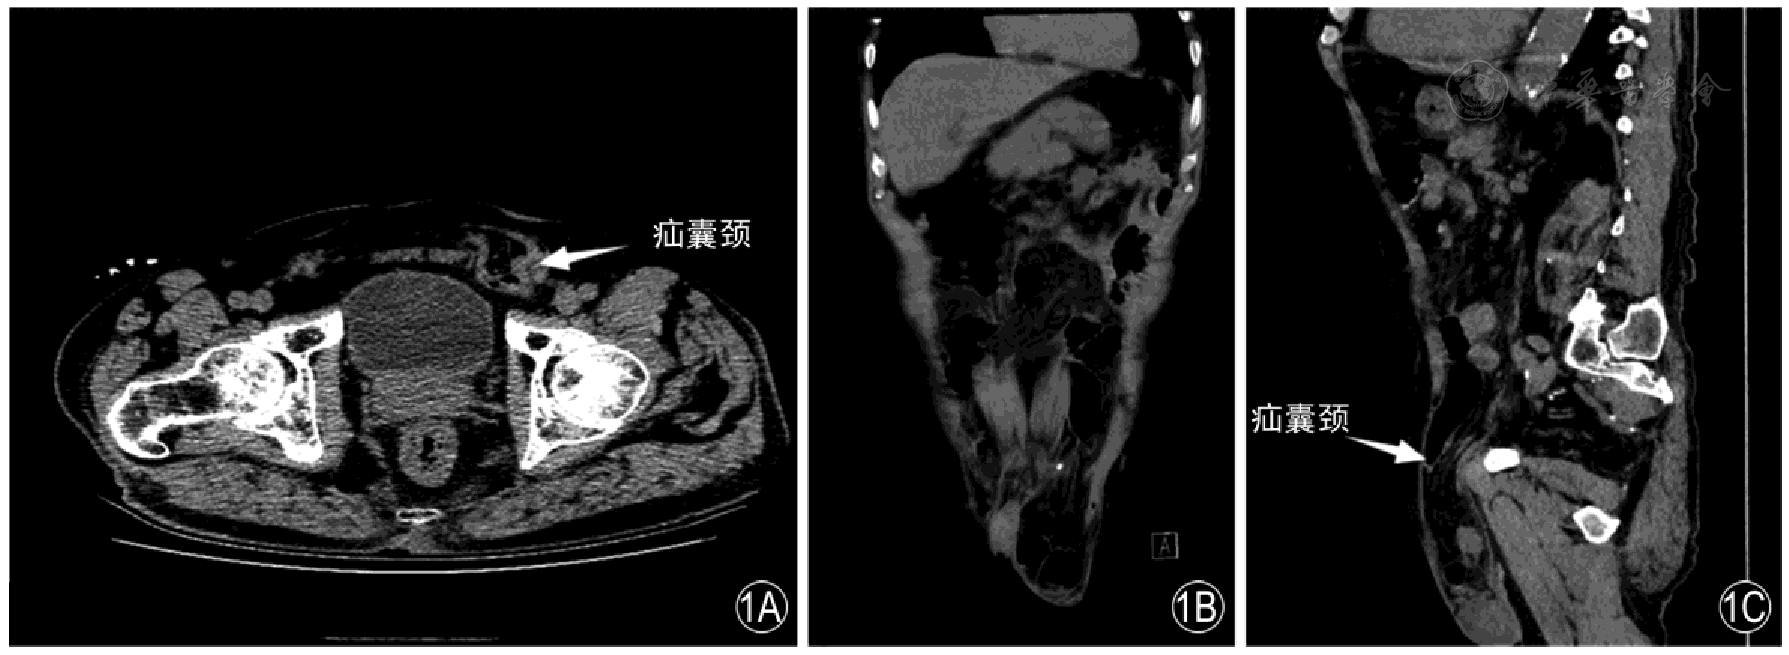

The sensitivity and specificity of MSCT in diagnosing inguinal hernias were 97.79% and 80.00%, respectively, with a kappa value of 0.652. The sensitivity and specificity of high-frequency ultrasound in diagnosing inguinal hernias were 96.32% and 80.00%, respectively, with a kappa value of 0.551. For the diagnosis of indirect hernias, MSCT had a sensitivity of 97.00% and a specificity of 94.44%, with a kappa value of 0.906; for the diagnosis of direct hernias, MSCT had a sensitivity of 94.44% and a specificity of 97.00%, with a kappa value of 0.906. High-frequency ultrasound had a sensitivity of 92.00% and a specificity of 88.89% for diagnosing indirect hernias, with a kappa value of 0.781, and a sensitivity of 88.89% and a specificity of 92.00% for diagnosing direct hernias, with a kappa value of 0.781. Indirect inguinal hernias presented with mixed density or were cystic-solid, all distributed on the anterior side of the inguinal ligament and lateral to the inferior epigastric artery, without a crescent sign or filling of the femoral triangle. Direct hernias were all distributed on the anterior side of the inguinal ligament and medial to the inferior epigastric artery, without filling of the femoral triangle, and often with a lateral crescent sign. The indirect hernia sac was located lateral to the origin of the inferior epigastric artery, and the diameter and shape of the hernia ring varied greatly. The direct hernia sac was located medial to the inferior epigastric artery, with no significant changes in the local abdominal wall, clear intestinal wall layers, no obvious hernia sac neck, and a small amount of fluid dark area could be detected in the hernia sac cavity of some patients. The hernia ring was located medial to the inferior epigastric vessels, and there was a small amount of color blood flow signal in the intestinal wall. The proportions of contents in indirect hernias were, in descending order: intestinal canal, greater omentum, ovary, effusion, intra-abdominal fat, and bladder. The proportions of contents in direct hernias were, in descending order: intestinal canal, intra-abdominal fat, greater omentum, effusion, ovary, fat, and bladder. After Bonferroni correction (corrected significance level of P<0.0083), there were no statistically significant differences in the detection rates of all contents between the two groups (all P>0.0083).